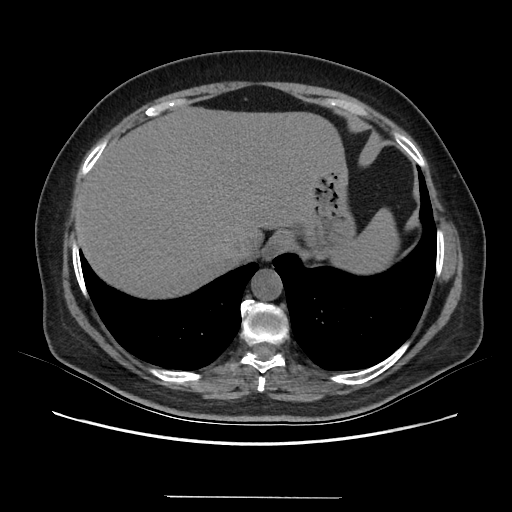

Generated VENOUS CT scan (A→B translation)

Full window (WL 1023.5, WW 4095 β†’ Low βˆ’1024, High +3071)

Actual HU range: [-1024.0, 864.1]